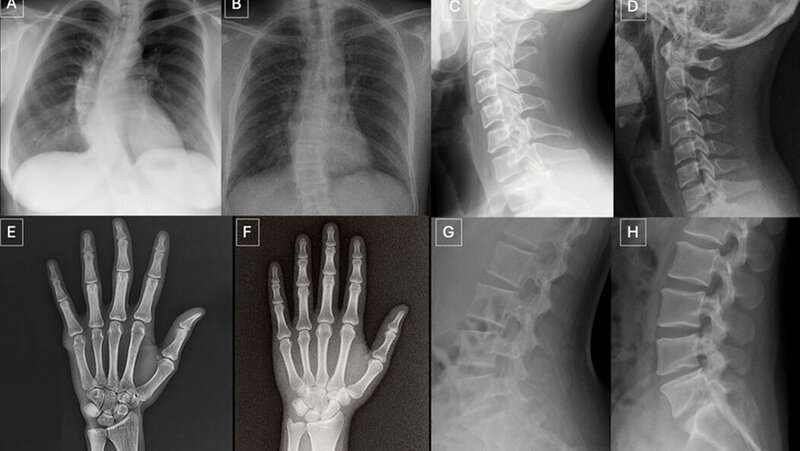

Heutige KI-Systeme können problemlos auf eine einfache Spracheingabe hin anatomisch plausible, fotorealistische Röntgenbilder erzeugen. Diese Möglichkeit wird heute bereits genutzt, um beispielsweise in der Ausbildung seltene Pathologien zu synthetisieren oder die Positionierung und Belichtung von Bildern systematisch zu variieren.

Zunächst wurden die Probanden nicht über den Studienzweck aufgeklärt und ihnen wurden 154 Röntgenaufnahmen verschiedener anatomischer Regionen (77 synthetische Bilder, generiert mit ChatGPT [GPT-4o; OpenAI], und 77 authentische Bilder) gezeigt. Nur sieben der 17 verblindeten Radiologen erkannten spontan die KI-generierten Bilder. Nachdem der Studienzweck bekannt war, glättete sich die Performance der Teilnehmer: Sie erreichten sie eine mittlere Genauigkeit von 74,8 Prozent (95 %-KI: 68,4–81,2) bei der Unterscheidung zwischen KI-generierten und realen Röntgenbildern. Die individuelle Genauigkeit lag zwischen 58,4 Prozent und 91,6 Prozent.